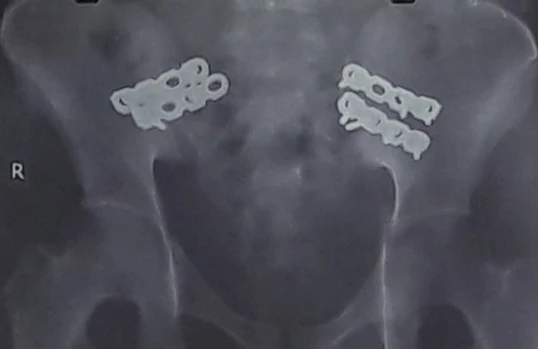

Xương chậu anh H. bị gãy và đã được cố định. Ảnh: BV CUNG CẤP

Tại BV quận 2, kết quả chụp X quang và MRI cho thấy anh H. gãy xương chậu, thủng tạng rỗng, chảy máu nhiều bộ phận. Anh H. còn rơi vào tình trạng nguy kịch do mất nhiều máu. Quá nóng ruột, người nhà nằng nặc yêu cầu BV chuyển anh H. lên tuyến trên.

Sau khi BV Chấn thương- Chỉnh hình có mặt, các BS của hai BV chia thành hai ê kíp phẫu thuật. Ê kíp 1 xử lý các vết thương hở, cầm máu, cắt bỏ một phần đại tràng giập nát và mở hậu môn tạm. Tiếp theo, ê kíp 2 cố định khung xương chậu bị gãy. Trong quá trình mổ, anh H. được truyền bốn đơn vị máu.